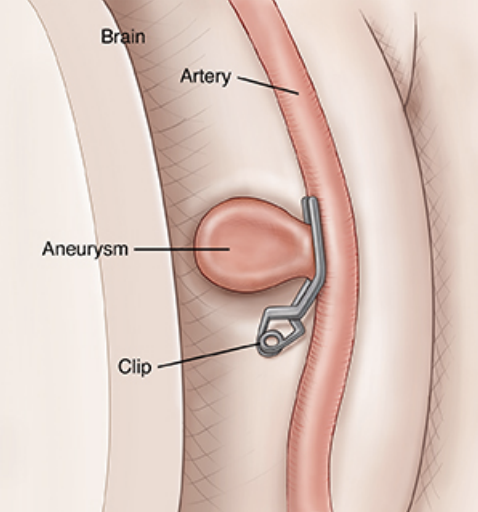

Brain Aneurysm

What is a Subarachnoid Hemorrhage? (click here)

Surgery for a Brain Aneurysm (click here)